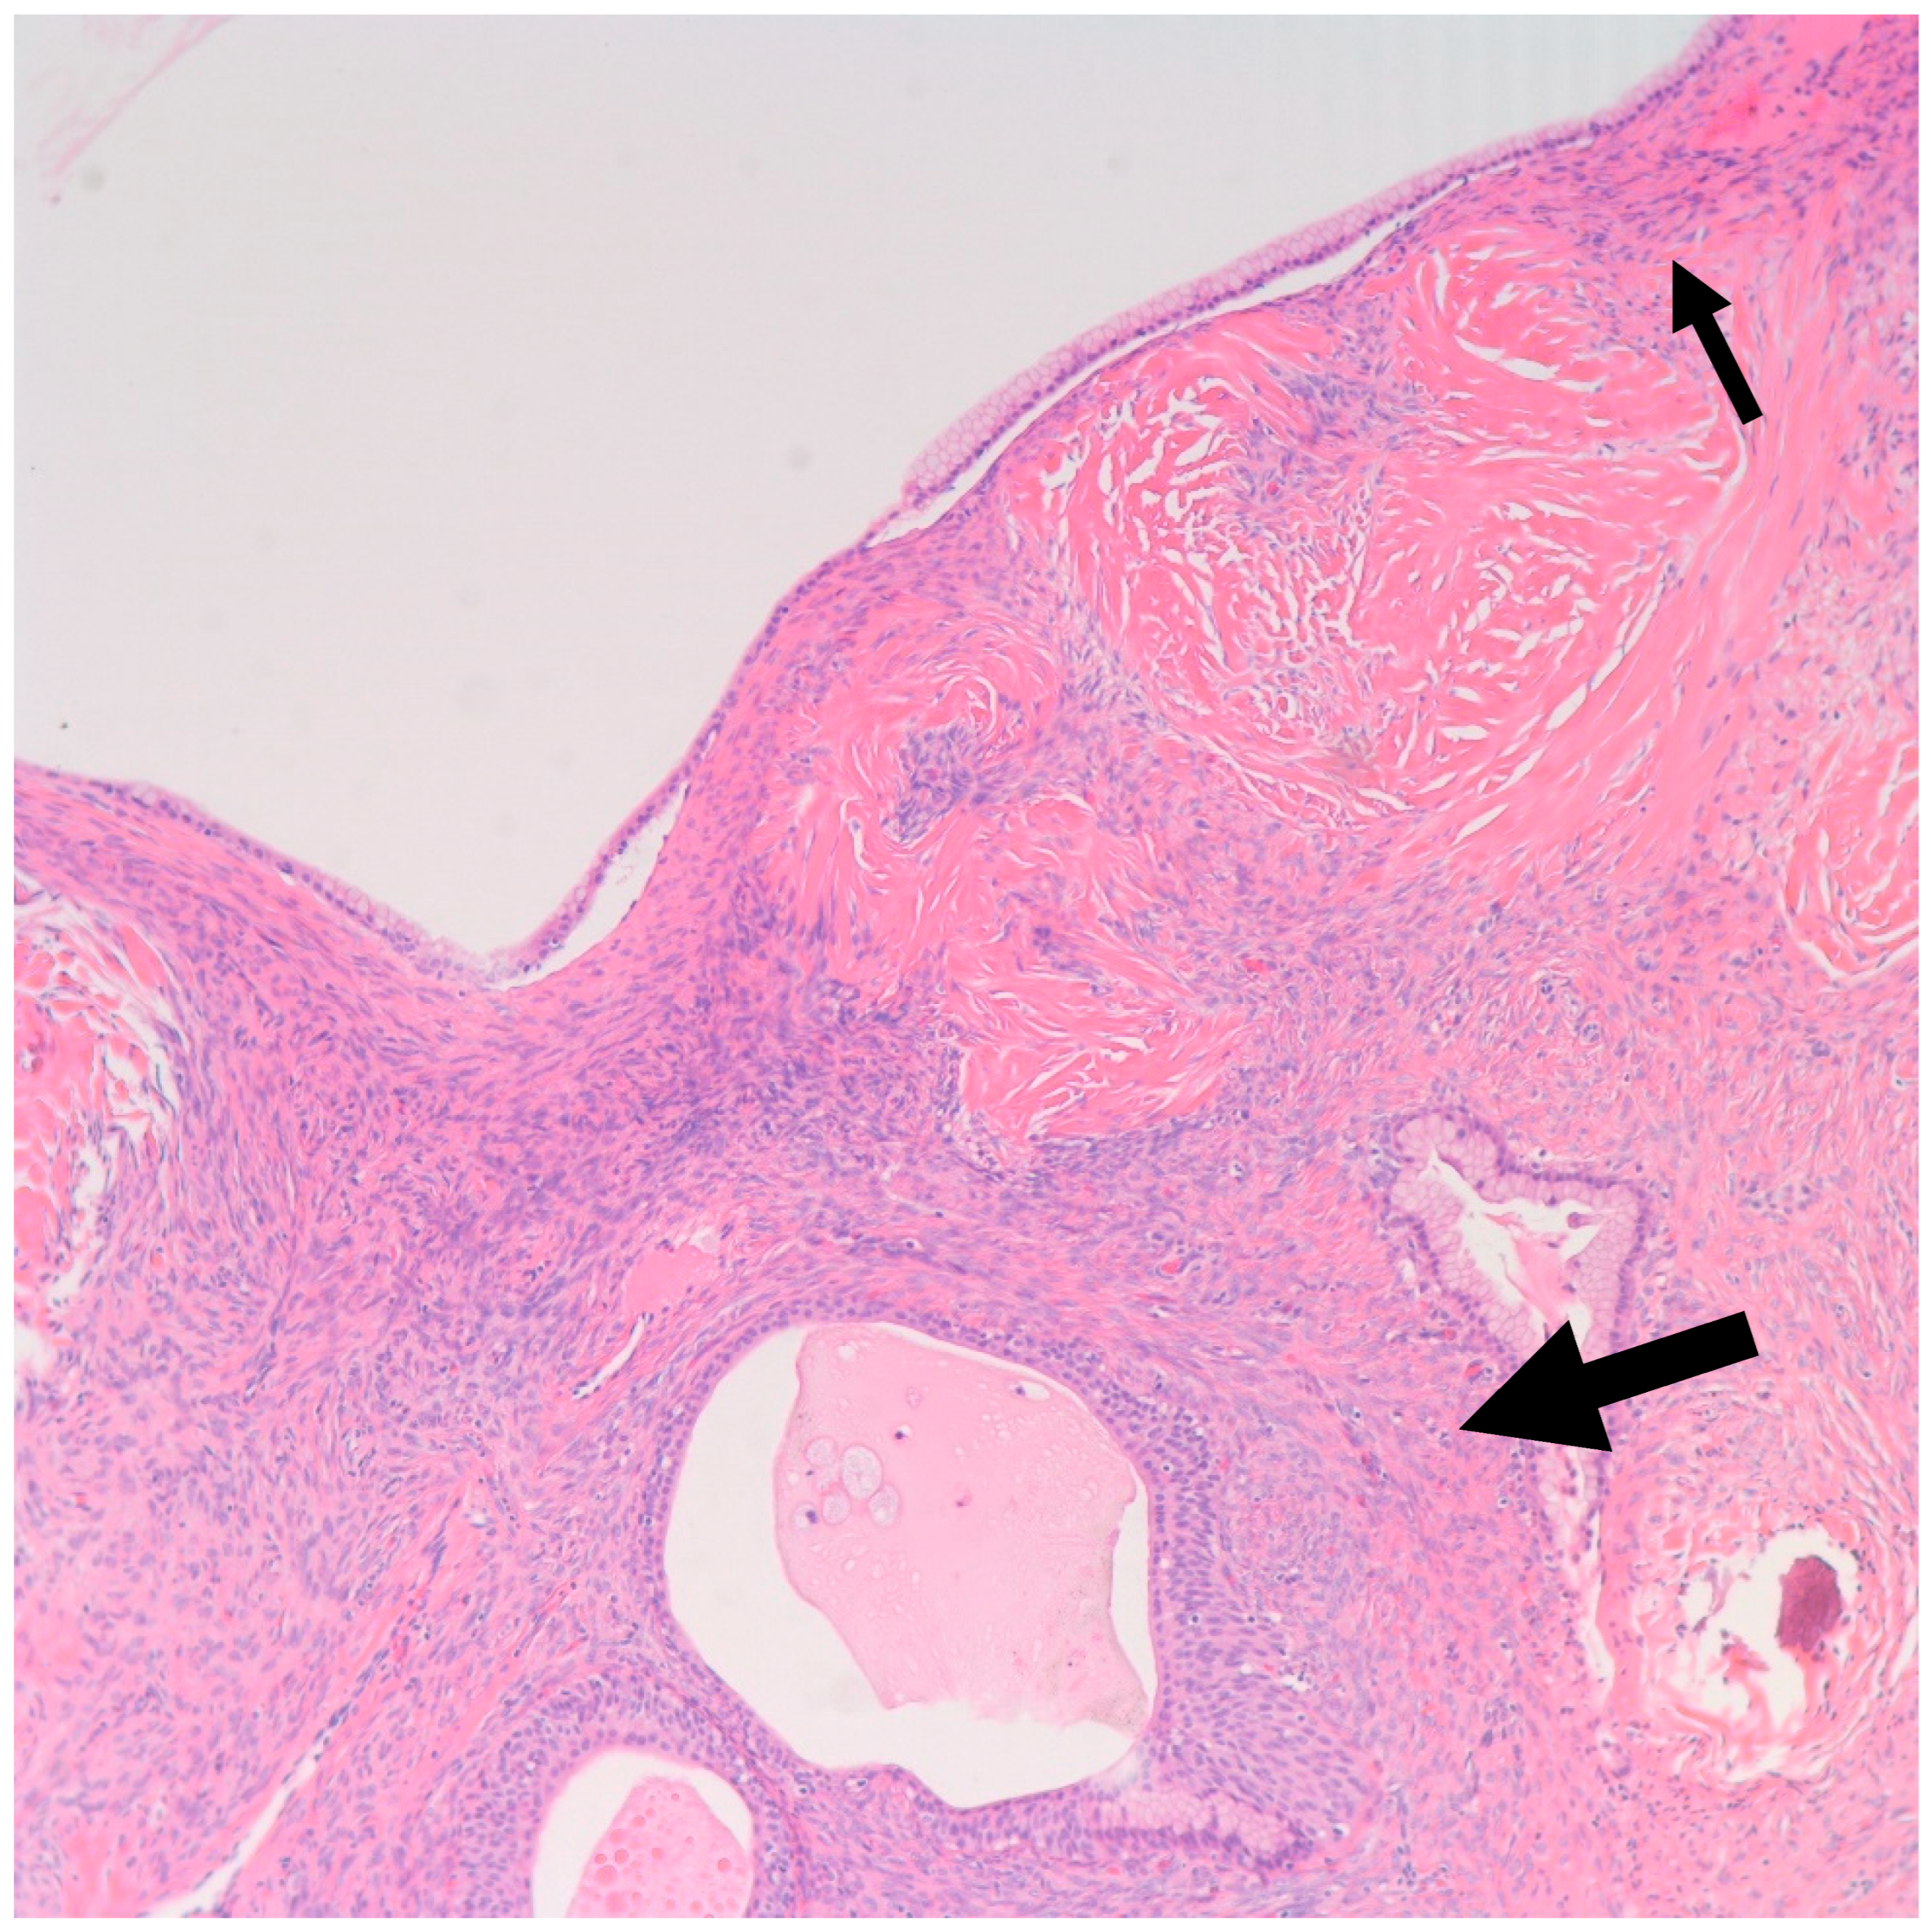

- Walthard cell rests: The differential diagnosis of benign BTs includes Walthard cell rests. Benign BTs contain a fibromatous background which is absent in Walthard cell rests.